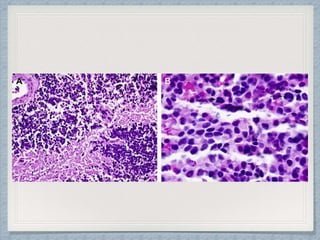

Microscopic Findings

Of Medulloblastoma

Microscopic variants

of

Medulloblastomas:

Classical.

Desmoplastic/Nodular.

Medulloblastoma with extensive nodularity.

Large cell variant/ Anaplastic.

Melanotic medulloblastoma.

Medullomyoblastoma.